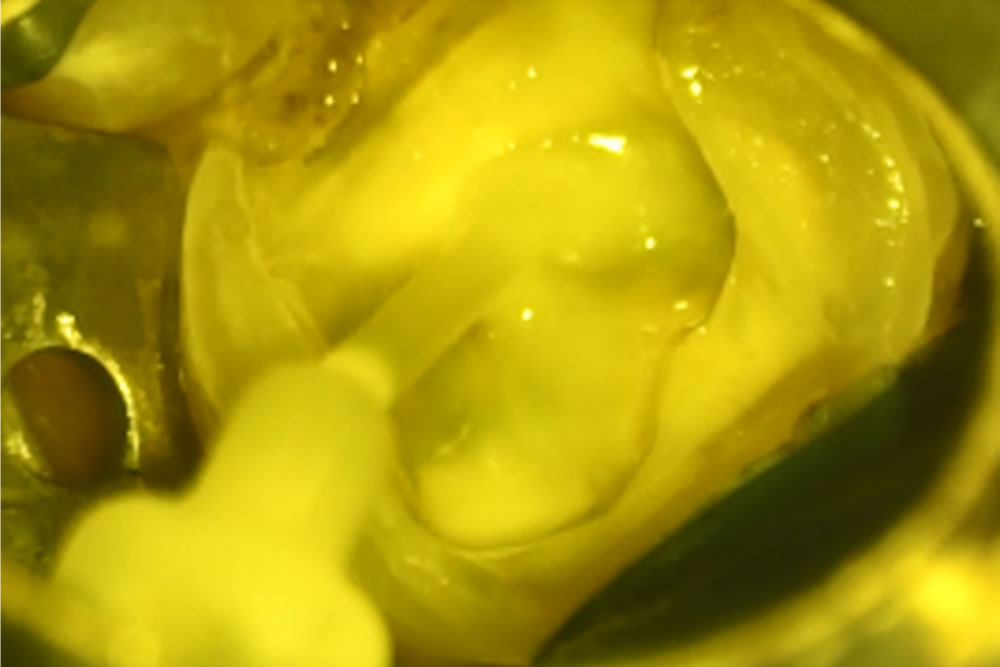

土台の形成

根の中に薬を詰めたら、歯の形を回復するためにまず土台となる部分を作ります。

レジンという歯の治療に用いるプラスチックの材料を、当該歯に流し込み特殊な光を当てて固めます。(マイクロスコープの強力なライトでも固まってしまうので遮光のため、視界が黄色くなっています。)

歯の表面をよく乾燥させ、接着のために歯の表面を薬品で処理します。ここでも呼気や唾液による接着不良を防止するため、ラバーダム防湿(ゴム製のシートで歯を口腔内から隔離)をしています。